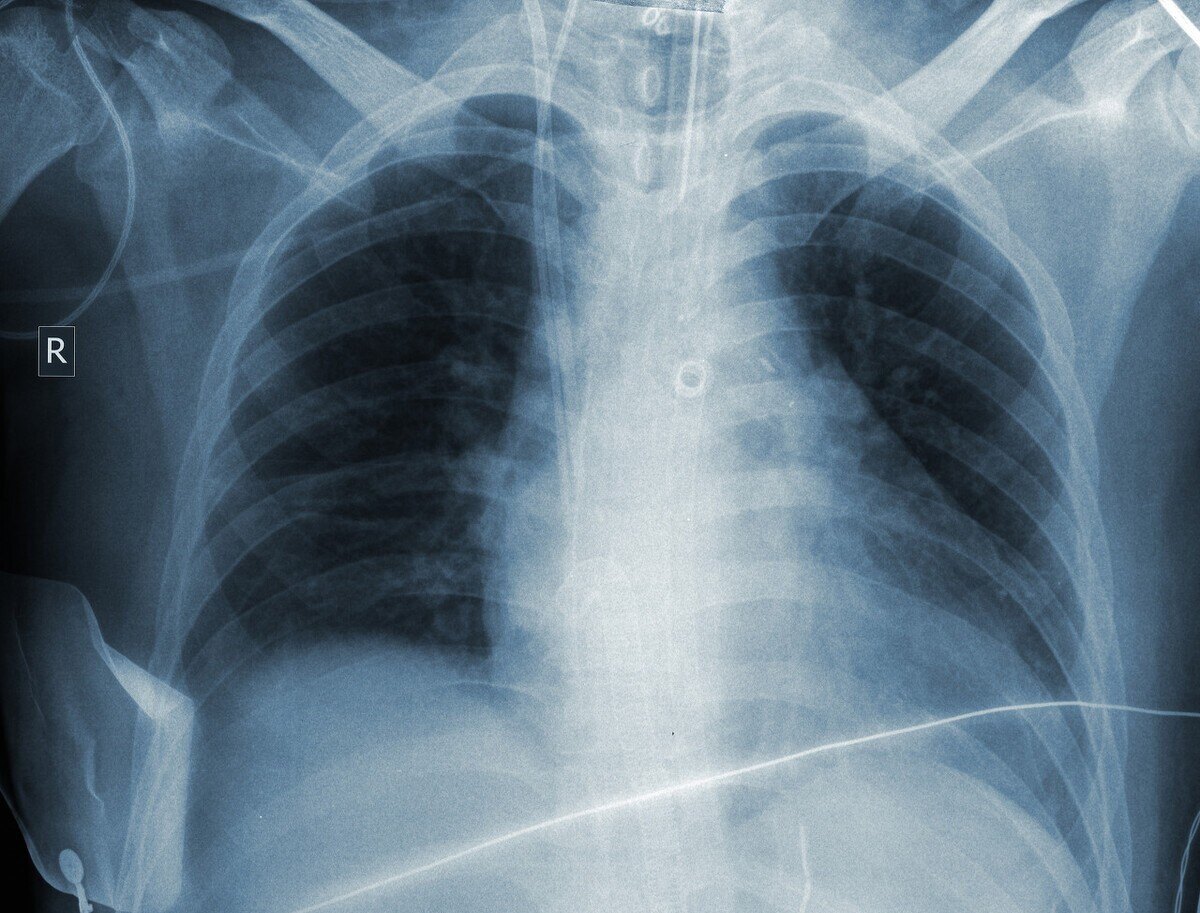

老陈来门诊就诊 , 自述近半个月散步时间久了就会气喘 , 怀疑是不是自己老慢支发了 , 过来查一查身体 , 不查不知道 , 一查吓一跳 , 老陈左肺上叶一个巨大肿块 , 有小孩拳头大小 , 从形态看 , 恶性肿瘤可能性非常大 。 安排了肺穿刺活检 , 病理提示肺鳞癌 。 经过PET-CT评估 , 没有淋巴结及其他脏器转移 , 胸外科认为可能考虑手术 , 或者先做2-3次新辅助治疗之后再手术 。

同一天来门诊的老杨 , 没有任何不适 , 抽了40年的烟 , 就是想常规体检一下 , 胸部CT发现左下肺1.5cm实性结节 , 形态不规则 , 考虑恶性 。 这个结果令老杨完全没想到 , 于是赶紧做了PET-CT , 在他等床位准备手术的时候 , PET-CT显示老杨的脑部顶叶有1cm病灶 , 胸椎3椎体见高代谢病灶 , 考虑转移瘤 。 经过肺穿刺活检病理 , 老杨的病理类型是小细胞肺癌 。